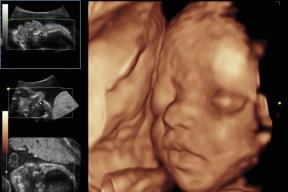

4D ULTRAZVUK: Pogledajte kako izgleda pregled i kako možete videti bebu (VIDEO)